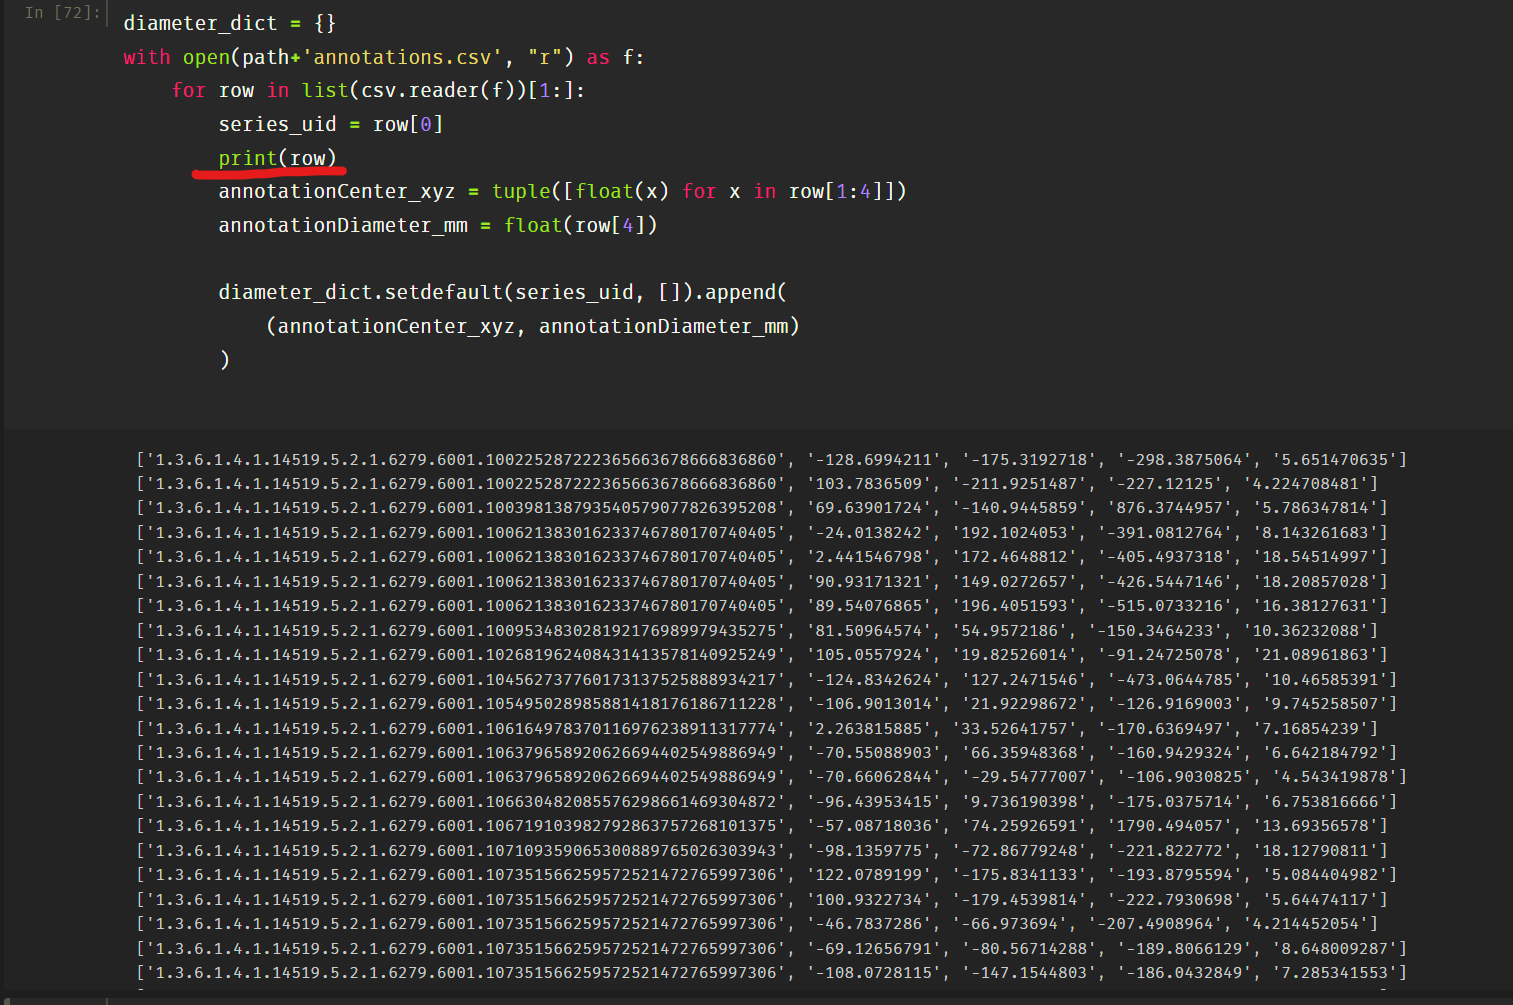

创建字典diameter_dict:

diameter_dict = {}

with open(path+'annotations.csv', "r") as f:

for row in list(csv.reader(f))[1:]:

series_uid = row[0]

annotationCenter_xyz = tuple([float(x) for x in row[1:4]])

annotationDiameter_mm = float(row[4])

diameter_dict.setdefault(series_uid, []).append(

(annotationCenter_xyz, annotationDiameter_mm)

)

功能解析:

把完整的每个 row 都打印出来看一下,发现就是一组组 List,所以 row[0] 就代表了第一列的 series_uid,row[1:4] 分别是位置坐标和 diameter :